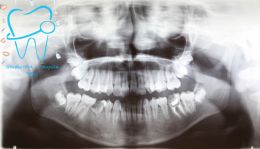

1982 visualizzazioni Una paziente di 12 anni si presenta alla nostra osservazione con una malocclusione in arcata superiore ed inferiore. La situazione appare complicata, oltre che da un affollamento notevole in arcata superiore, dalla agenesia dell'elemento 4.5 e con il 3.6 molto distrutto e difficilmente recuperabile per il futuro in maniera pervedibile. Si decide a questo punto per un trattamento ortodontico fisso con il movimento mesiale degli elementi posteriori e la chiusura degli spazi solo con denti sani e pienamente funzionanti ed evitare successivamente costosi procedimenti protesici.